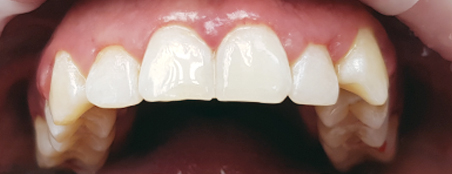

Наши работы

Перед началом лечения делаются цифровые фотоснимки полости рта. Эти съемки регулярно повторяются, чтобы фиксировать изменения в положении зубов. Еще один способ оценить масштаб проблемы – изготовить гипсовые модели челюстей, чтобы пациент мог убедиться в изменении положения зубов и общей запущенности болезни. Кроме того, на такой модели врачу удобнее проводить все необходимые измерения.